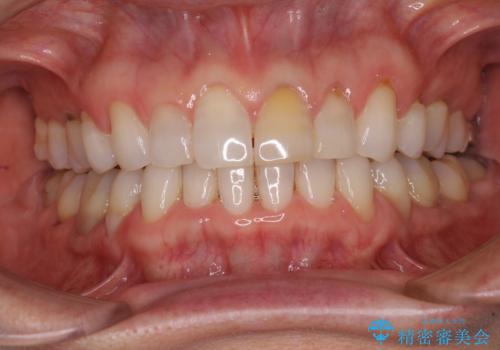

矯正治療の後戻り インビザライン・ライトでの再矯正

- 上下前歯を中心に、以前行った矯正治療の後戻りが気になるとのことで来院された患者様です。

後戻りは軽度であったため、インビザライン・ライトにて治療を行うこととしました。

矯正治療後は、再度後戻りすることを極力回避するために、下顎前歯の舌側を細いワイヤーを用いて保定することとしました。